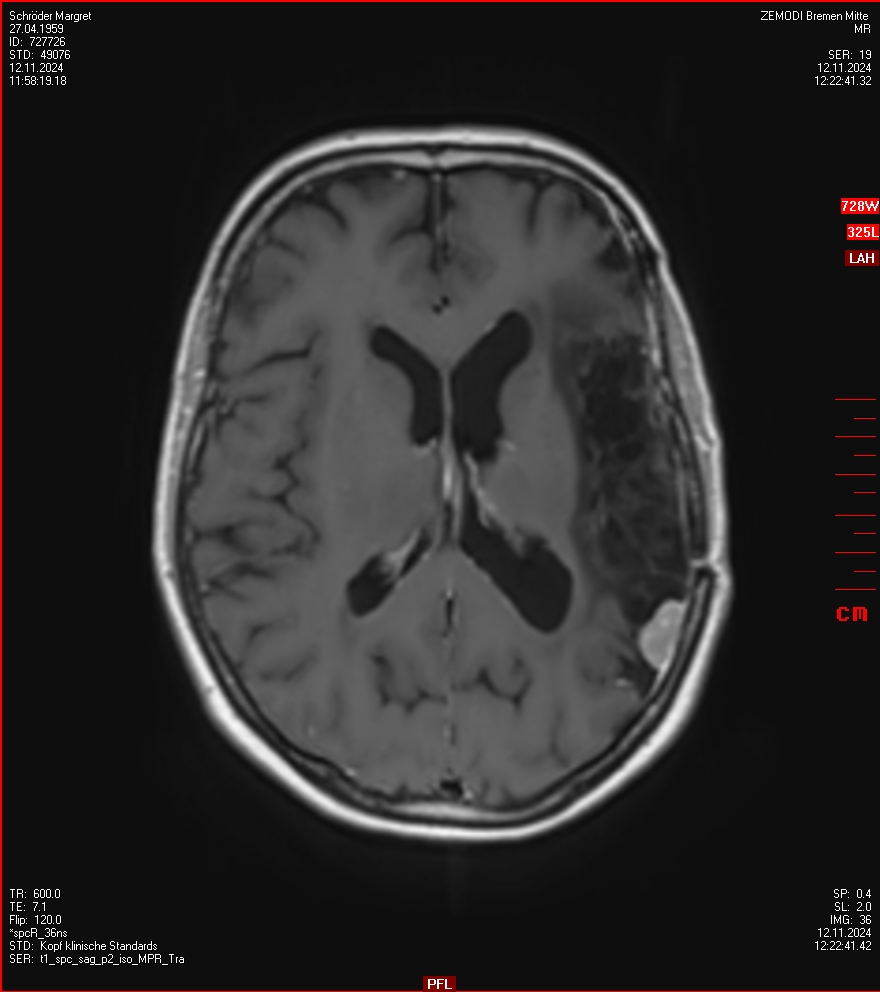

MRT vom 12. November 2024

So nun ein paar neue Bilder aus meinem Kopf. (Durch klicken bekommt man eine größe Ansicht eines Einzelbildes).

Die letzten drei Bilder Zeigen aus meiner Sicht den Tumor, der im Jahr 2021 bestrahlt wurde.

Ich denke, in den letzen 12 Monaten sind da ein paar Rezidive gewachsen,  vor 12 Monaten waren sie auch schon zu erkennen - vorher noch nicht. Nun hoffe ich auf den Rat des Spezialisten. Hoffendlich kann man etwas machen.